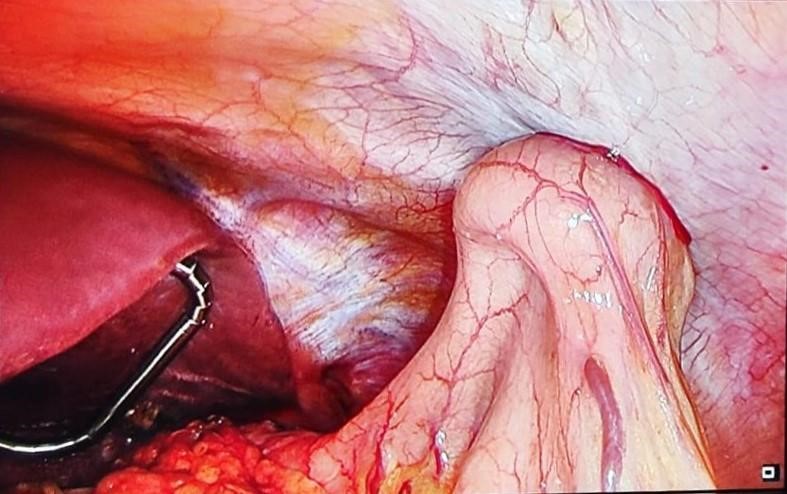

A la exploración, abdomen no doloroso y sin signos de irritación peritoneal. En la radiografía de tórax se observa imagen de hernia hiatal a nivel del tórax con nivel hidroaéreo (imagen 1). Se realiza gastroscopia informada de posible volvulación a nivel subcardial. En TC se observa dilatación sacular y focal de la región subcardial gástrica por encima del diafragma, con imagen de miga de pan y moderada cantidad de líquido libre, ausencia de restos alimentarios significativos en esófago distal y resto del estómago y sin signos de perforación de víscera hueca, hallazgos compatibles con volvulación subcardial. Se solicita tránsito esofagogástrico que es informado de recidiva herniaria sin afectación de la motilidad (imagen 2).

Se libera funduplicatura previa de adherencias a pilares diafragmáticos mediante abordaje laparoscópico, consiguiendo el descenso de la misma a cavidad abdominal. Se aproximan los pilares diafragmáticos con un punto de material irreabsorbible y se coloca malla Gore Bio-A fijada con PDS a los pilares diafragmáticos (imagen 3). Se realiza gastroscopia intraoperatoria hasta alcanzar segunda porción duodenal sin visualización de signos de sufrimiento mucoso ni estenosis en ninguna localización y se coloca PEG endoscópica en cara anterior de cuerpo distal como gastropexia (imagen 4).

Imagen 3. Cruroplastia con malla Gore Bio-A.

Imagen 4. Gastropexia mediante colocación de PEG endoscópica en cara anterior de cuerpo gástrico.